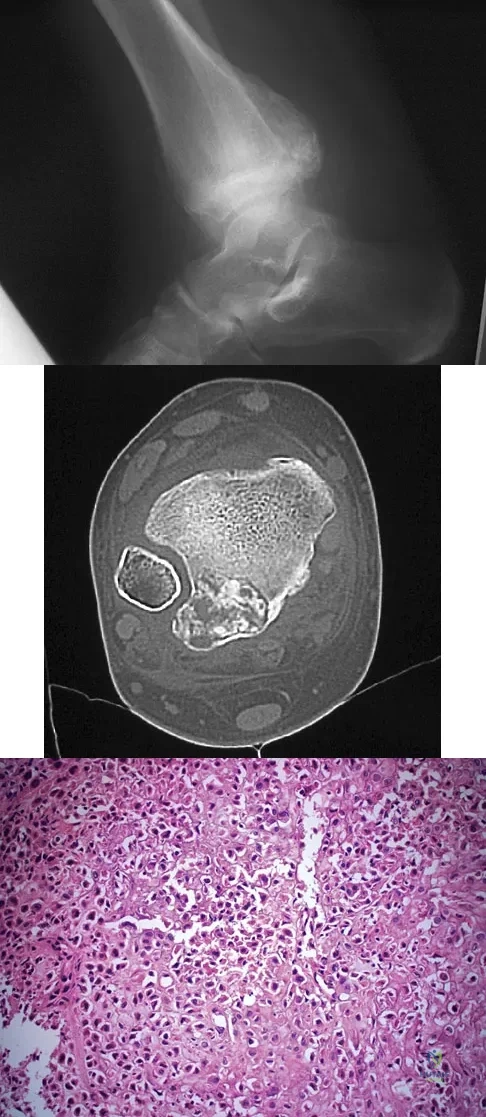

A 23-year-old man has had right posterolateral knee pain and occasional lateral calf dysesthesias for the past 8 months. A radiograph, CT scan, MRI scans, and a biopsy specimen are shown in Figures 62a through 62e. What is the most likely diagnosis?

A 16-year-old girl has had hip pain for 1 year. Approximately 2 months ago she noted the development of a hard mass in the right buttock that has steadily increased in size. She now reports severe pain in the right buttock, with radiation down the leg and numbness involving the right foot and toes. A radiograph is shown in Figure 70a and an axial postcontrast T1-weighted MRI scan is shown in Figure 70b. A biopsy specimen is shown in Figure 70c. The chest CT shows multiple lung metastases. Treatment of this lesion should consist of

A 13-year-old boy has had pain and swelling in his ankle for the past several months. Based on the radiograph, MRI scan, and biopsy specimen shown in Figures 77a through 77c, what is the best course of action?